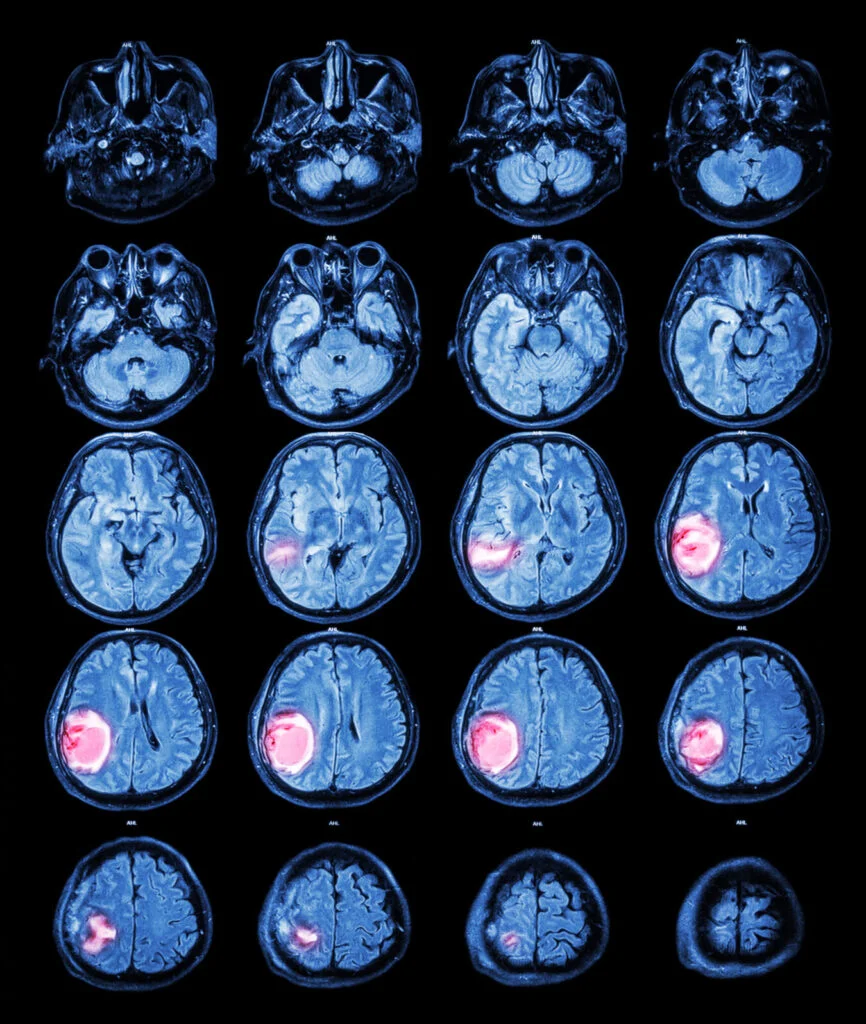

Tumors are abnormal cell proliferation in the body and constitute a broad category of cancerous diseases. Tumors consist of cells that grow and multiply abnormally, continuing to grow irregularly and out of proportion to healthy body tissue. Tumors are generally divided into two main types: benign tumors and malignant tumors.

Malignant tumors are cancerous tumors that often spread to another organ in the body due to rapid cell growth, which is often life-threatening.

The importance of early diagnosis of tumors lies in helping to accurately determine the degree of disease progression. It's worth noting that stage IV is the last and most dangerous stage of cancer, meaning the tumor has spread to many areas of the body and is therefore difficult to control.